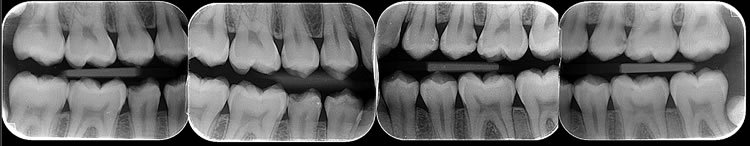

* Interproximal ou Bite-wing

O exame radiográfico interproximal é realizado através de um sensor ( 3 cm X 4 cm) para a visualização das coroas, terço

cervical das raízes e cristas ósseas alveolares dos elementos dentários superiores e inferiores. Indicado principalmente para

o diagnóstico de lesões cariosas e avaliação das cristas ósseas alveolares.